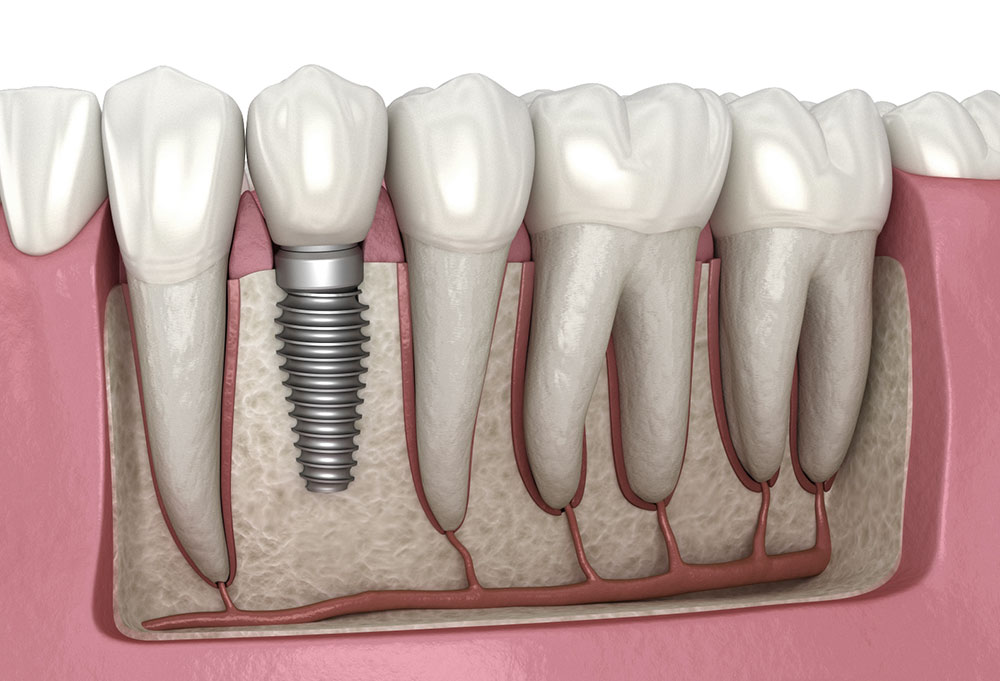

Dental Implants

Dental implants are advanced dental service offering permanent tooth replacement.

Why Dental Implants Are Effective?

Implants integrate with jawbone, providing unmatched stability. These dental services prevent bone loss and maintain facial structure.